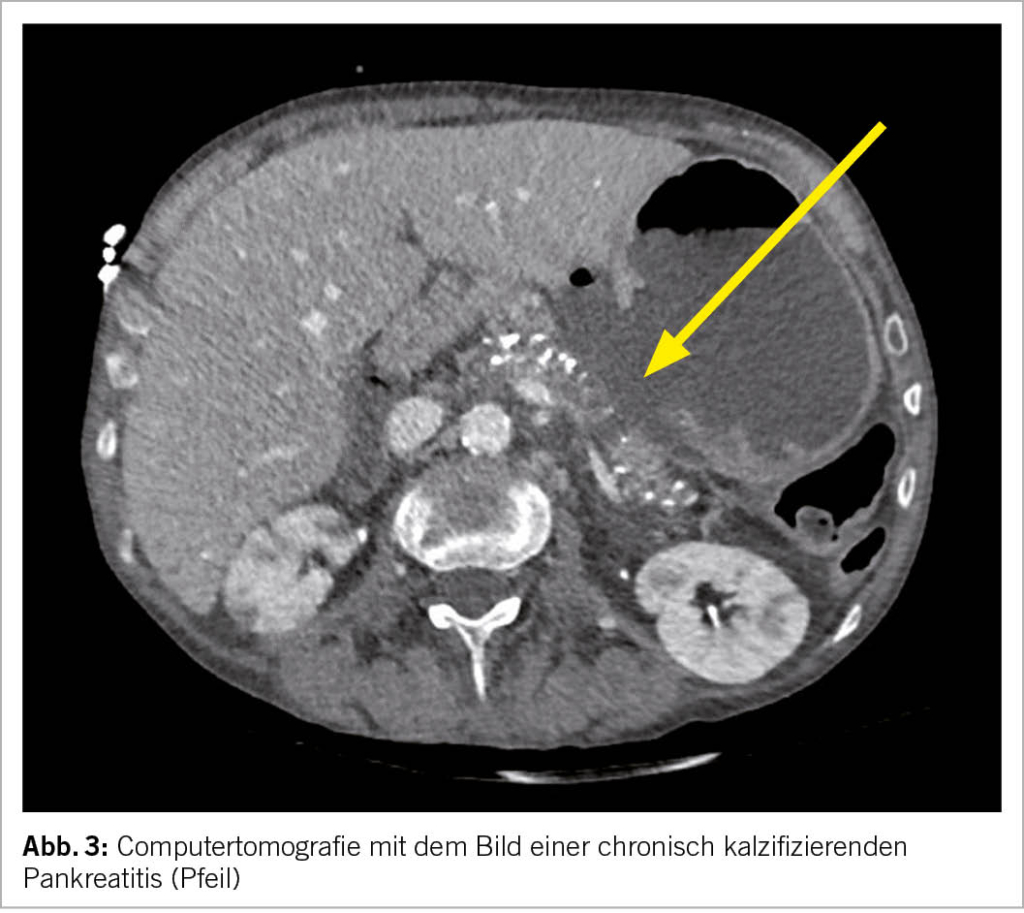

Die Bildgebung ist eine der wichtigsten Bestandteile der Diagnostik. Die Verfahren der Wahl mit hoher Spezifizität und Sensitivität sind die Endosonografie (Endoskopischer Ultraschall, Abk. EUS, Bild 2), die Computertomografie (Abk. CT, Abb. 3) und die Magnetresonanztomografie (Abk. MRI). Die transabdominale Sonografie kann das Pankreas leider häufig nur ungenügend darstellen, dient aber als kostengünstige und breit verfügbare initiale Untersuchung. Die Zeichen der chronischen Pankreatitis bestehen u.a.

aus einem erweiterten, irregulären Hauptgang, Pankreatikolithen (Abb. 2), Verkalkungen (Abb. 3), hyperechogene Foci und Septen, lobuliertes Parenchym, Atrophie (Abb. 3) und ev. lokale Komplikationen (Tab. 1).

Alle bildgebenden Methoden haben ihre Vor- und Nachteile und sollten idealerweise mit einer Fachperson je nach Fragestellung vorbesprochen werden, um Doppeluntersuchungen zu vermeiden. Die EUS eignet sich v.a. zur Detektion früher Stadien der chronischen Pankreatitis. Suspekte Befunde können diagnostisch punktiert werden und lokale Komplikationen wie Pseudozysten oder Walled-off Nekrosen können endoskopisch behandelt werden. Die CT stellt Kalk (Abb. 3) äusserst zuverlässig dar. Falls der Verdacht auf Pankreaskarzinom besteht, sollte zwecks Beurteilung der Resektabilität ein spezifisches Pankreasprotokoll sowie eine Thorax-CT angemeldet werden. Das MR empfiehlt sich mit dem MRCP Zusatzprotokoll, um den Gallen- und Pankreasgang darzustellen.